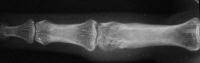

Case 2. Mass developing after a lateral dislocation of the proximal  interphalangeal joint of a 34 year old woman.

Radiographs were consistent with either a united collateral ligament avulsion fracture or ossiification of a parosteal hematoma.